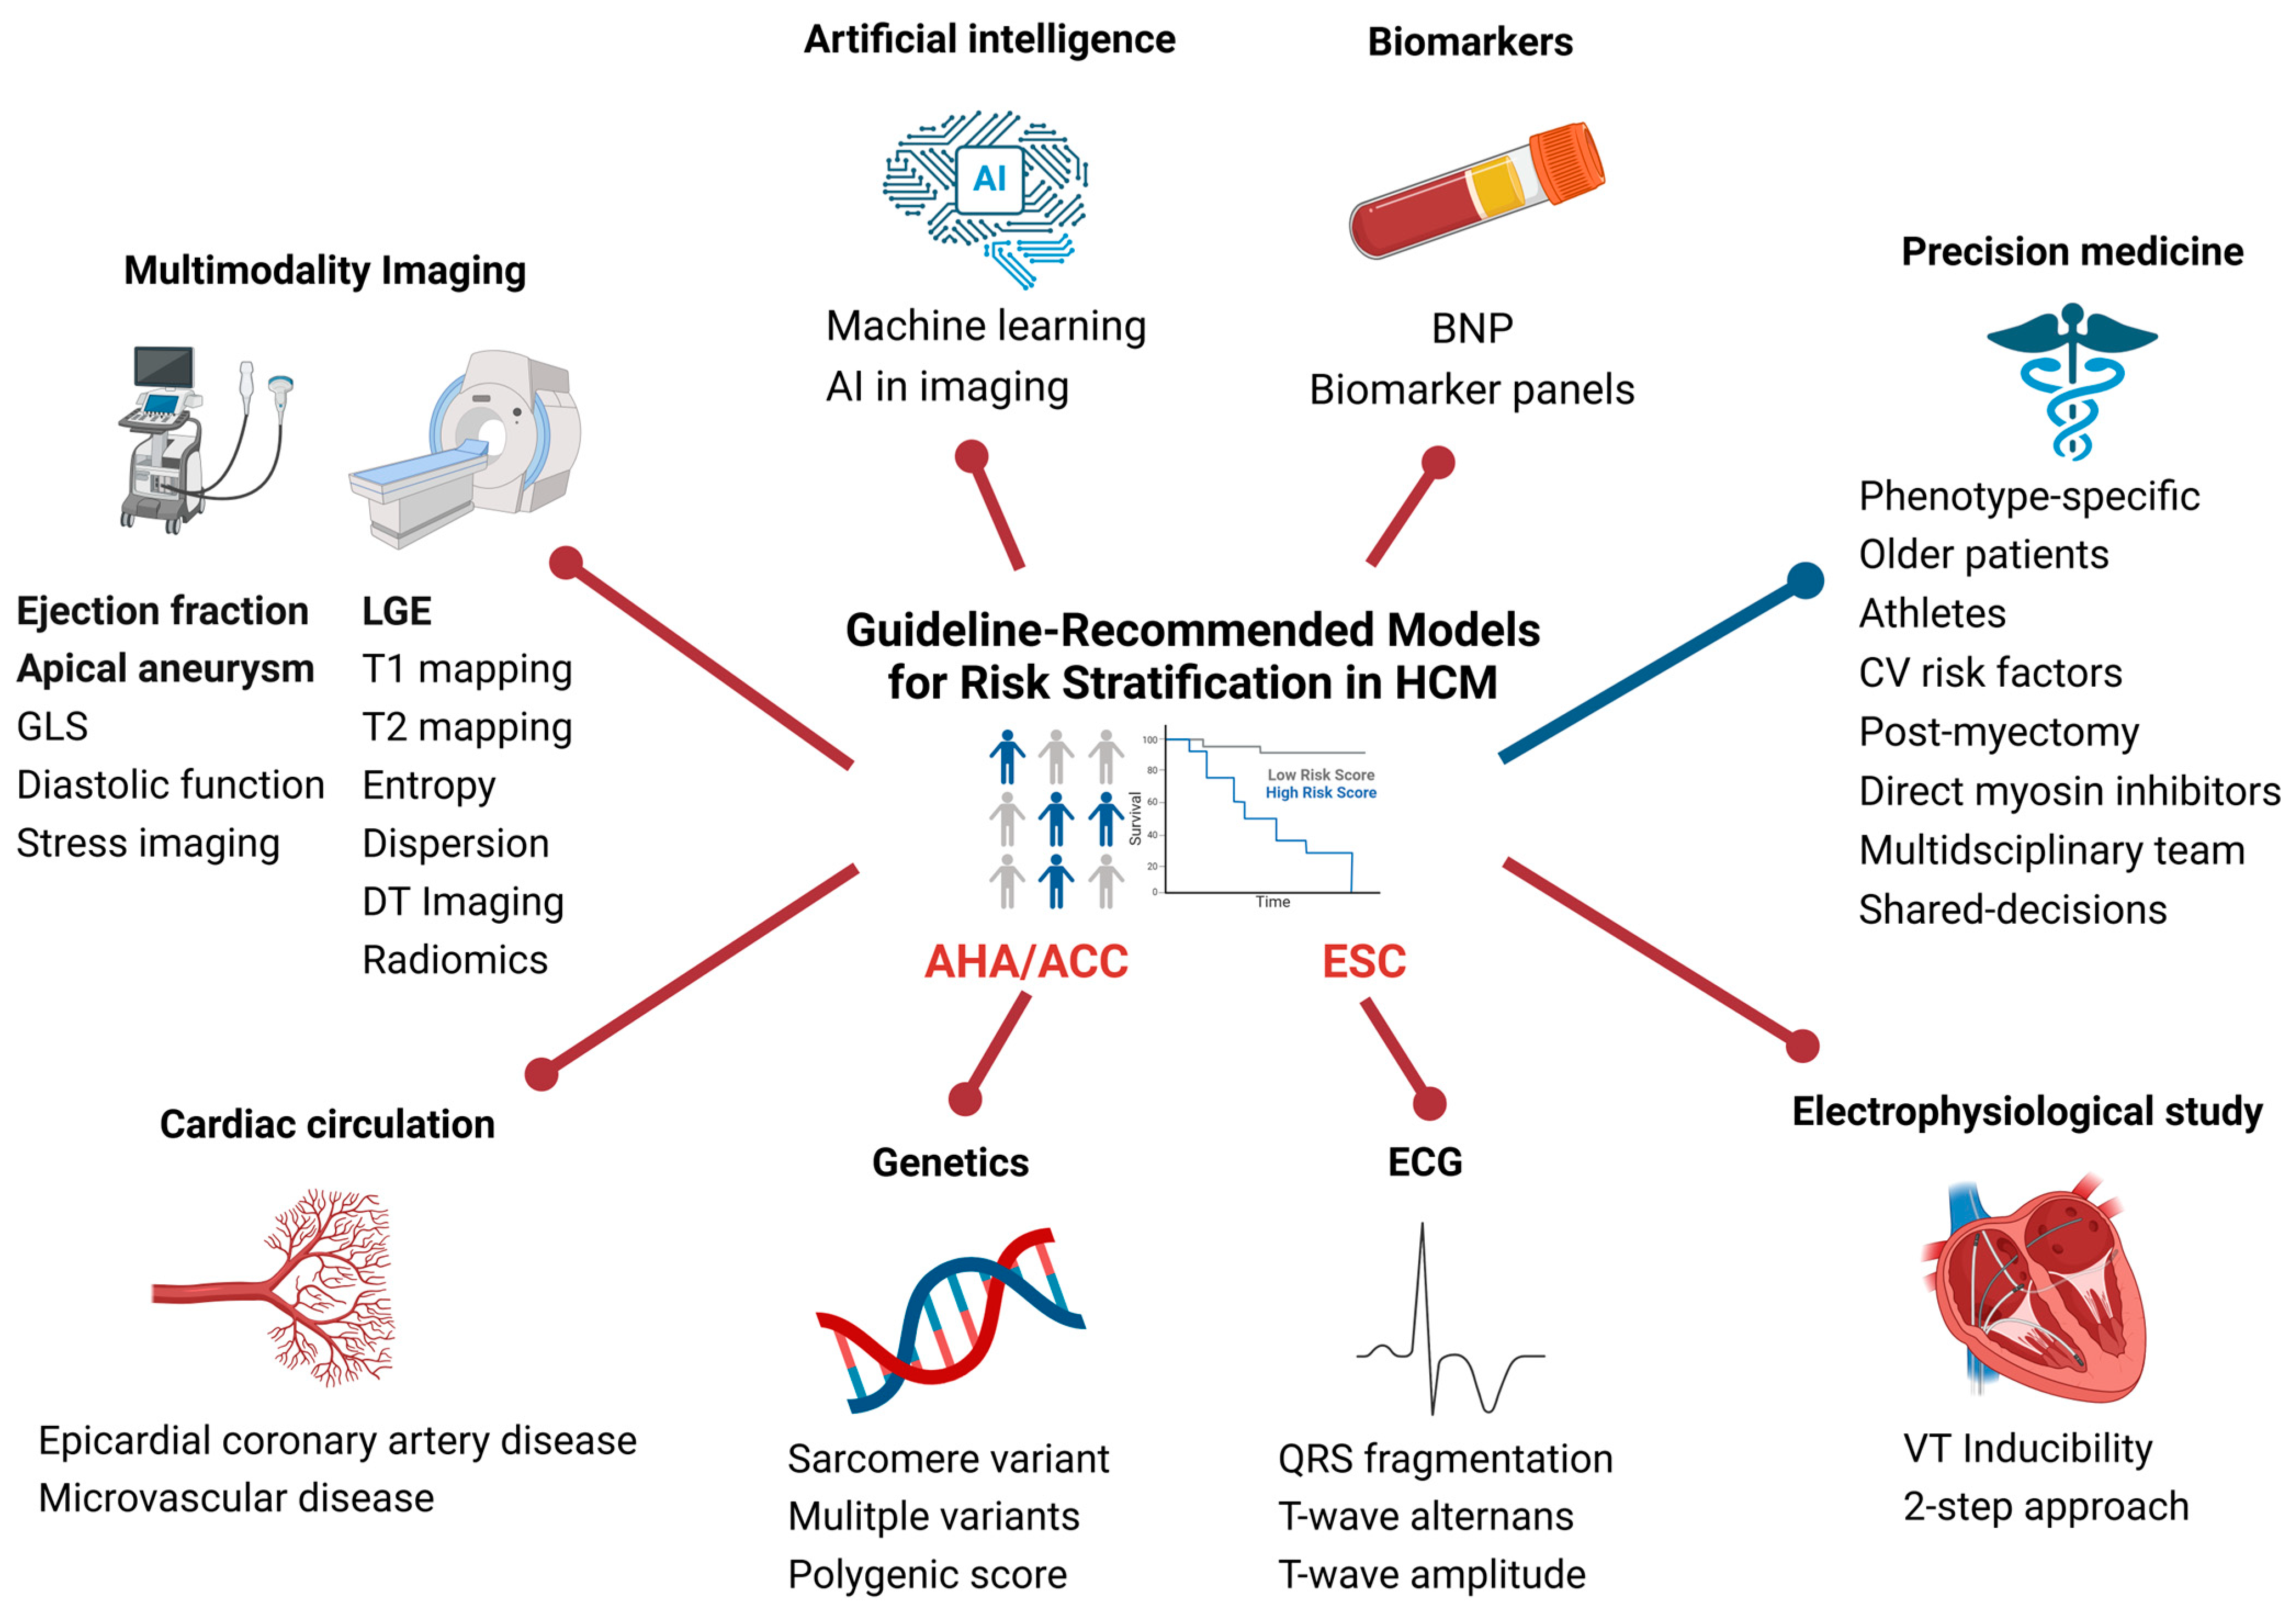

2. Current Risk Stratification Models

7. Electrophysiological Testing

8. Novel Approaches to Risk Stratification in Hypertrophic Cardiomyopathy

8.2. Multimodality Imaging

8.3. Artificial Intelligence

9. Conclusions